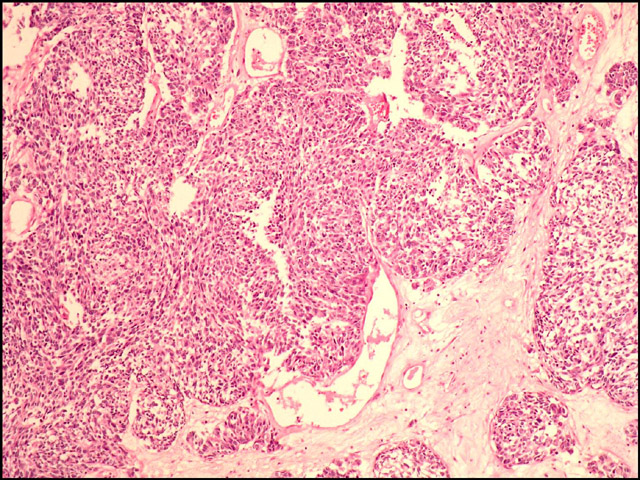

Descripción microscópica: el estudio histológico de ambas lesiones demuestra un carcinoma de células pequeñas que ulcera la epidermis, infiltra dermis e hipodermis e invade vasos linfáticos. La parte superficial de la neoplasia presenta un crecimiento difuso a expensas de células pequeñas y de tamaño intermedio (fig. 2). Además, se identifican focos de diferenciación escamosa (fig. 3) y áreas glandulares tapizadas por epitelio cúbico mucosecretor (fig. 4 y 5), adoptando una morfología que simula un carcinoma mucoepidermoide (fig. 6). También se advierten zonas con patrón angiomatoide, con formación de lagos hemáticos revestidos por células neoplásicos de mayor tamaño.

Carcinoma de células pequeñas.